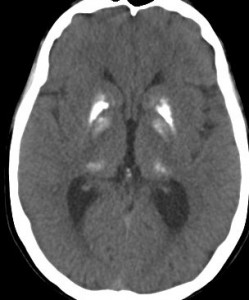

20年以上前のことですが,髄芽腫の1歳6ヶ月の子どもに25グレイの全脳照射をしました。これは15年後のCTです。

脳の萎縮は目立ちません。認知機能は低いのですが支援を受けて学校へ行けています。下垂体機能は低下して成長ホルモンなどの補充をして普通に暮らせています。

CTで,両側の大脳基底核(被殻と淡蒼球)と視床後部に石灰化がみられます。乳幼児期に放射線治療を受けた子どもに見られるものです。